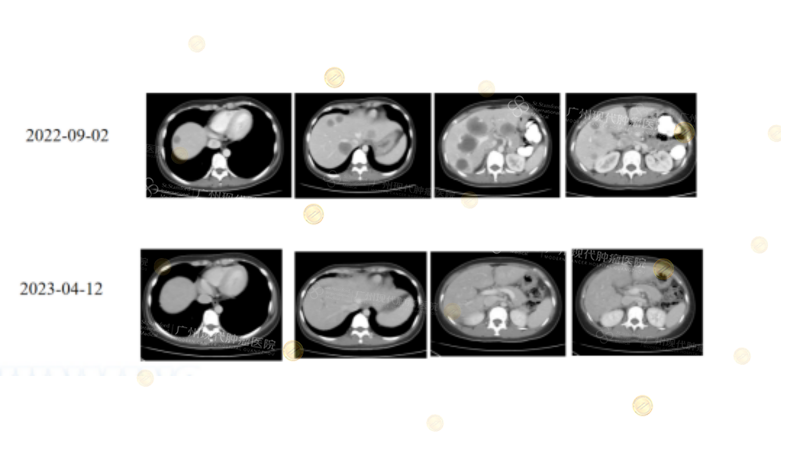

Exploration of Precision Biotherapy Regimens for Rare Genetic Subtypes

Notable clinical outcomes attracting international attention were achieved in patients with mutations such as BRAF, ARID1A, and elevated TMB.

(Note: 36-year-old female with hepatic flexure colon cancer (BRAF/ARID1A mutation, MSS, slightly elevated TMB). Liver metastasis progressed after multiline therapy. Fourth-line combined biotherapy (Nivolumab+Ipilimumab ± Regorafenib) achieved PR/SD, with PFS of 15 months, showing benefit from precision biotherapy in rare genetic subtypes.)